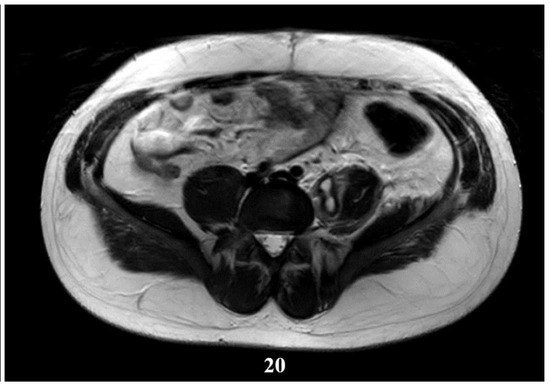

Figure 20.

T2W sequence, axial—Postoperative residual hydatid cyst located at the level of the left psoas muscle and deep to the left gluteus maximus muscle (part 1).

Deep from the gluteus maximus muscle on the left side, there are multiloculated, multiple septate intralesional, relatively well delimited areas, which seem to communicate both with each other and with lesions of a similar appearance located in the thickness and adjacent to the quadratus femoris muscle on the left side, with total dimensions in the coronal plane of approximately 11.3/6.4 cm, with the most likely appearance of parasitic cysts (Figure 19, Figure 20 and Figure 21).